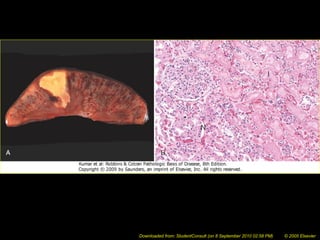

Enzymatic Fat Necrosis

• Results from hydrolytic action of lipases

on fat

• Most often seen in and around the

pancreas; can also be seen in other

fatty areas of the body, usually due to

trauma

• Fatty acids released via hydrolysis react

with calcium to form chalky white areas

 “saponification”

Enzymatic fat necrosis of

pancreas -- gross

Fat necrosis -- micro

Enzymatic Fat Necrosis •Results from hydrolytic action of lipases on fat • Most often seen in and around the pancreas; can also be seen in other fatty areas of the body, usually due to trauma • Fatty acids released via hydrolysis react with calcium to form chalky white areas  “saponification”

Enzymatic fat necrosisof pancreas -- gross